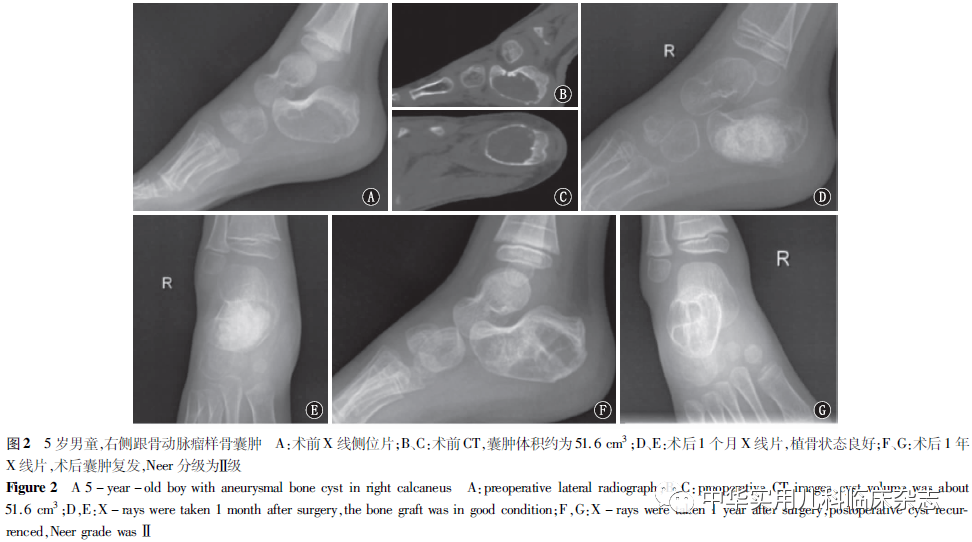

结果2.1 临床特点 共纳入符合标准的病例29例,其中男19例,女10例;年龄3.6~14.0岁,平均9.2岁,其中≤10岁组12例,>10岁组17例;发生在股骨近端9例(31.0%),肱骨近端5例(17.2%),腓骨近端4例(13.8%),其余11例(37.9%)发生在中远端;26例(89.7%)有局部压痛,25例(86.2%)有不同程度的疼痛,18例(62.1%)有局部肿胀,15例(51.7%)有关节功能障碍,12例(41.4%)合并病理性骨折。根据Enneking分期标准判定:静止期18例(62.1%),活跃期7例(24.1%),侵袭期4例(13.8%)。估算囊肿体积大小范围为3.3~172.0 cm3,中位数体积约为50.8 cm3;囊肿至骺板距离范围为0~85.0 mm,中位数距离为20.8 mm(表1)。2.2 复发因素分析 所有患儿术后随访2.2~10.1年,平均3.8年。28例患儿局部疼痛和肿胀消失,关节功能恢复良好,仅1例出现轻微跛行,髋关节活动稍受限。术后根据Neer影像学分级标准判定:Ⅰ 级2例,Ⅱ级4例,Ⅲ级8例,Ⅳ级15例。6例(20.7%)患儿为术后复发,复发时间为术后2.5~20.3个月,平均12.5个月。其中≤10岁组复发4例,病理性骨折组复发3例,囊肿体积>50.8 cm3组复发6例,静止期组复发1例,活跃期和侵袭期组复发5例(45.5%),囊肿至骺板距离≤20.8 mm组复发3例(表1,图1、2)。